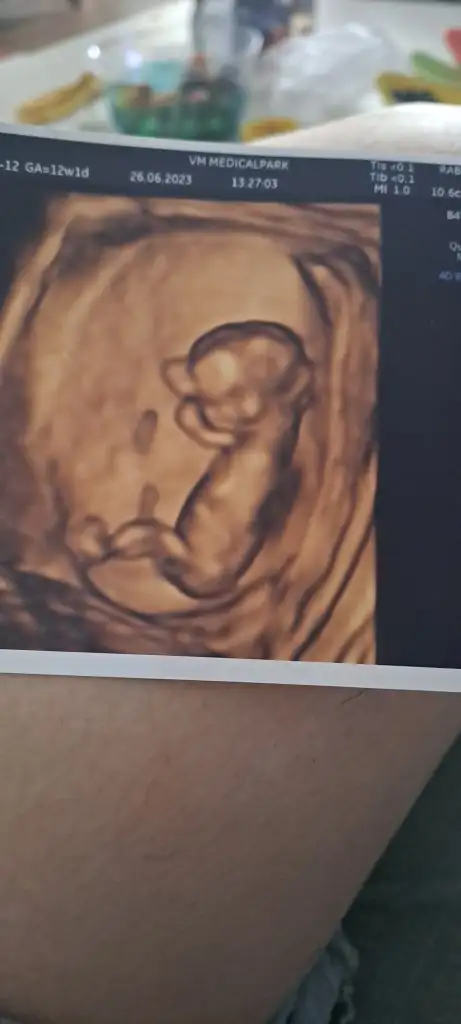

Z Zzzzz00 canım bana da tahminde bulunur musun lutfen 12+1 haftalik teşekkür ederim

Kızlar ultrason fotolarınızı atın 6 ve 7.hafta ya da 11. 12. 13. Hafta yorumlayayim. Amacım kesin bilmek değil net bi şey söyleyemem ancak ultrason net olursa daha iyi olur :)